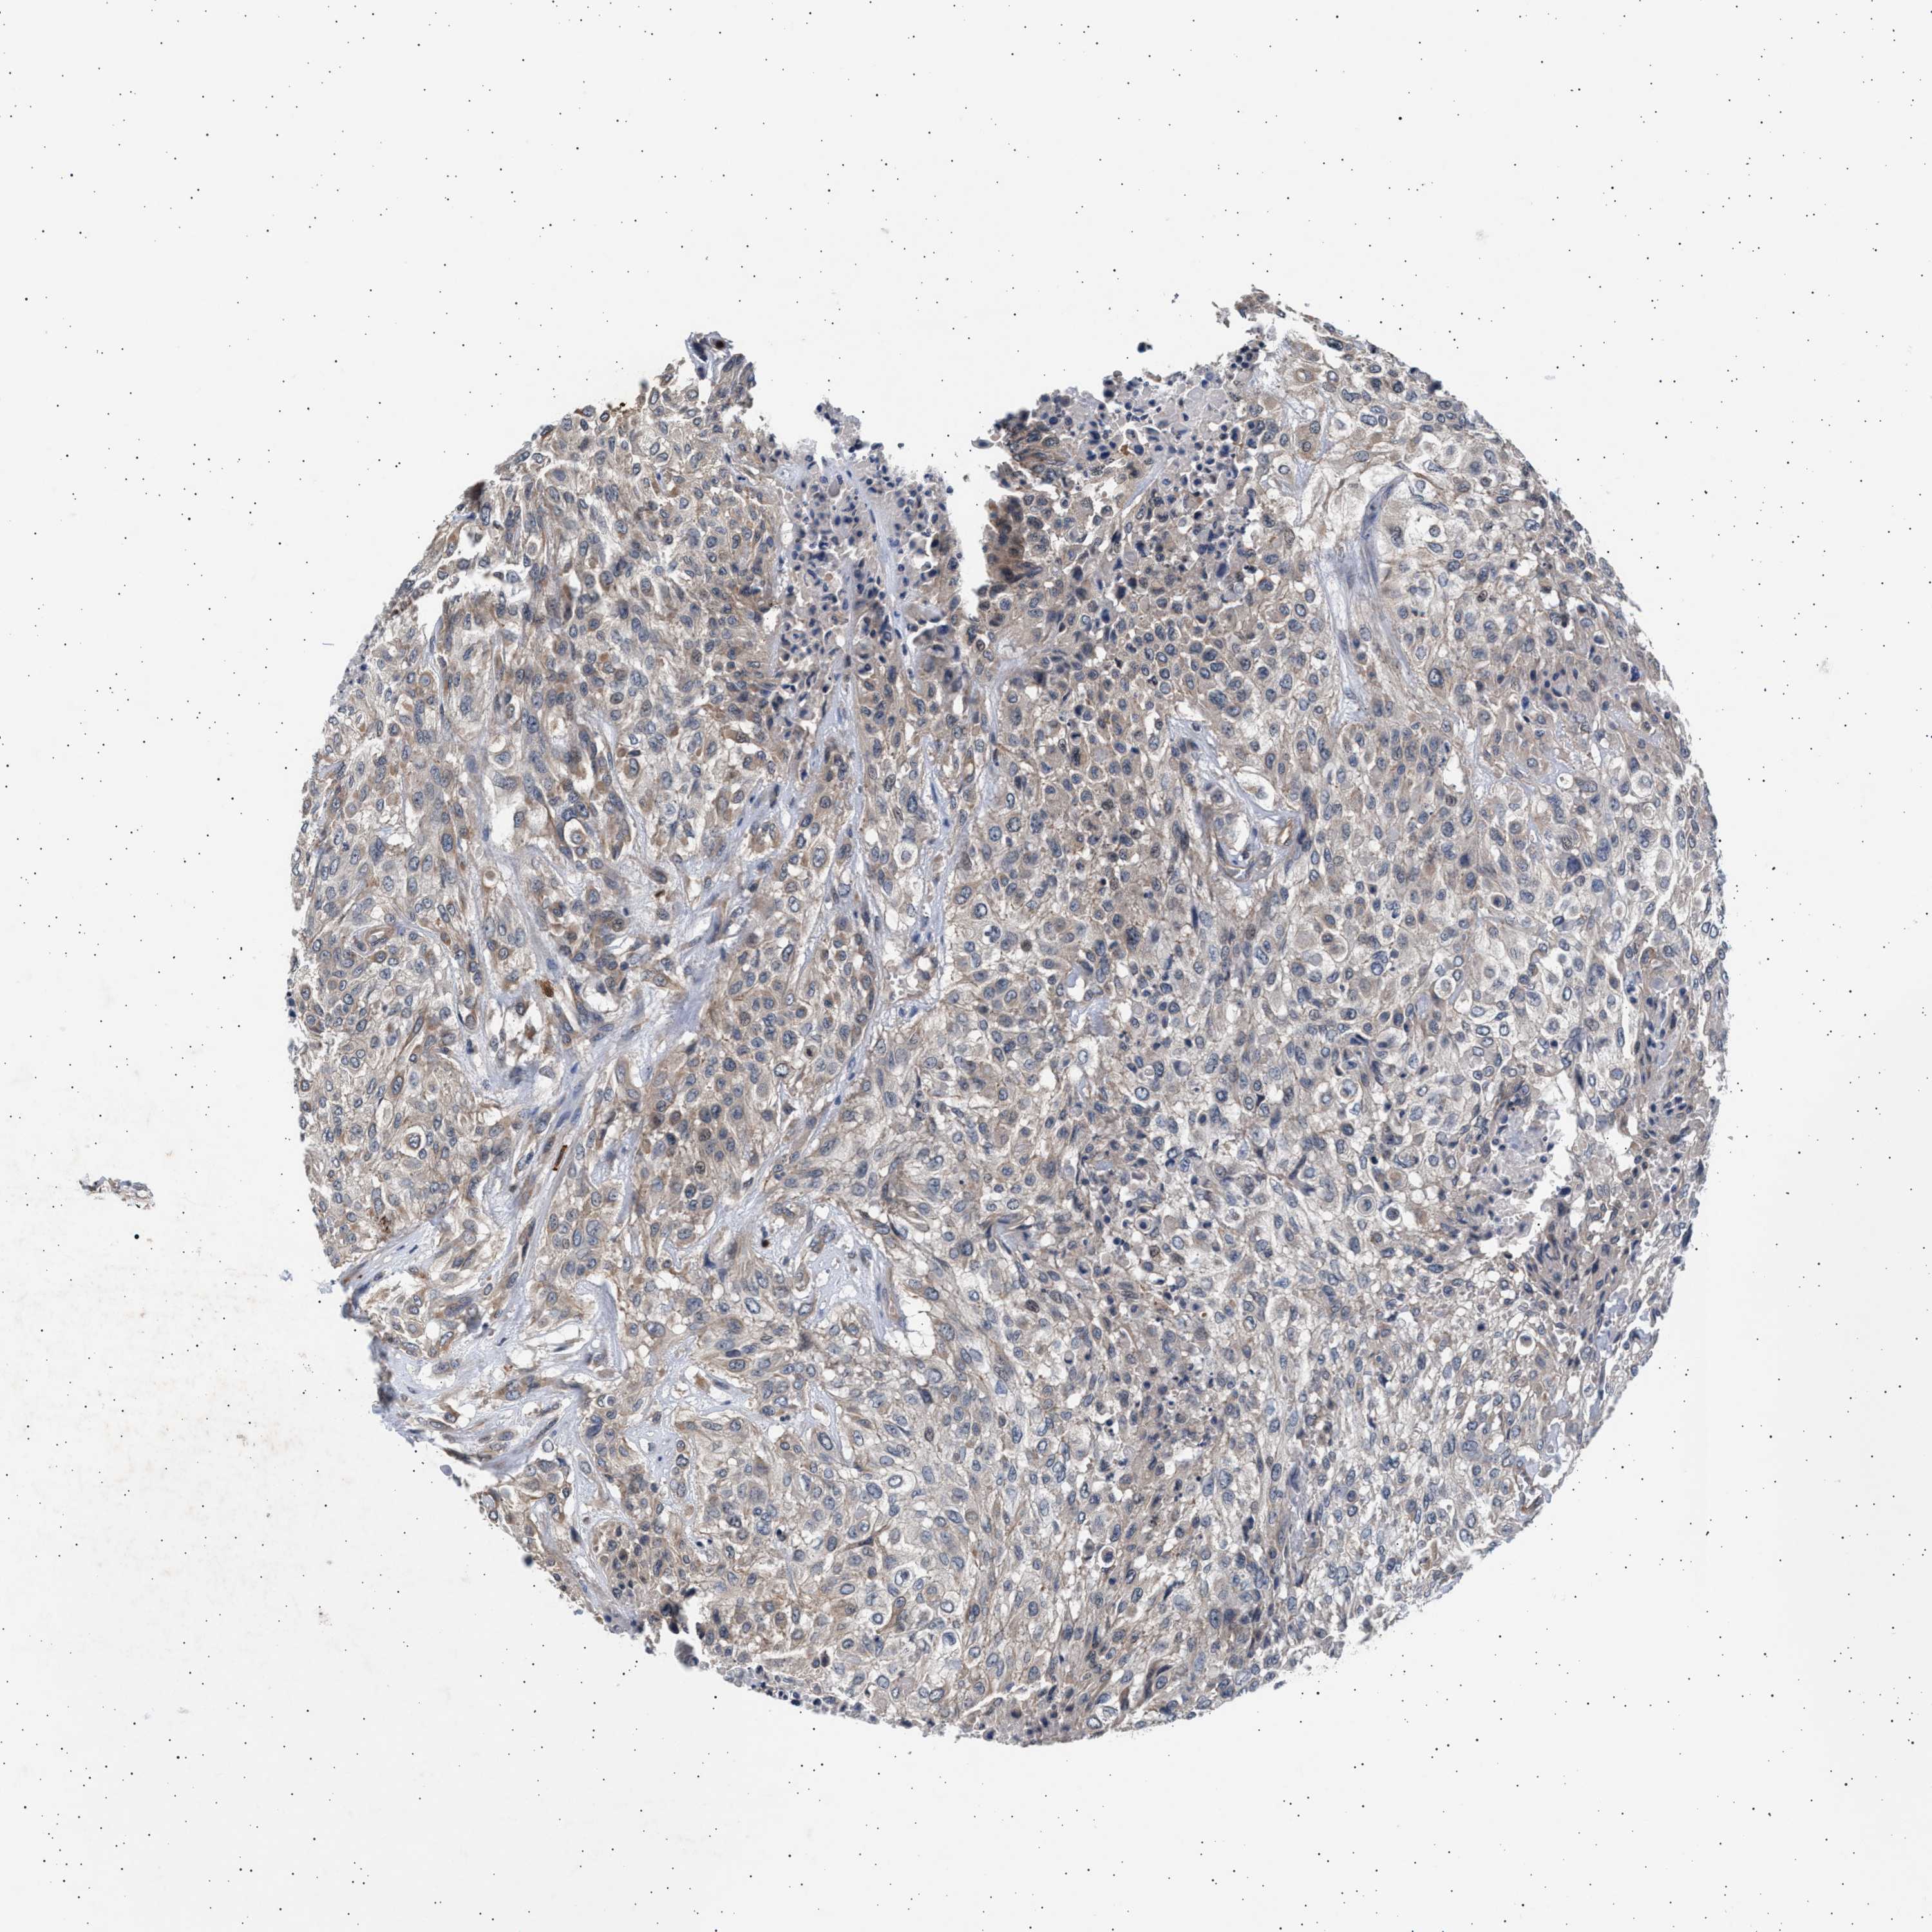

UROTHELIAL CANCER - Protein expressioni

A mouse-over function shows sample information and annotation data. Click on an image to view it in a full screen mode. Samples can be filtered based on level of antibody staining by selecting one or several of the following categories: high, medium, low and not detected. The assay and annotation is described here.

Antibody stainingi

Antibody staining in the annotated cell types in the current human tissue is reported as not detected, low, medium, or high, based on conventional immunohistochemistry profiling in selected tissues. This score is based on the combination of the staining intensity and fraction of stained cells.

Each image is clickable and will lead to virtual microscopy that enables deeper exploration of all samples and also displays staining intensity scores, fraction scores and subcellular localization as well as patient and tissue information for each sample.

Antibody HPA005788

Antibody CAB022073

Staining

High

Medium

Low

Not detected

Intensity

Strong

Moderate

Weak

Negative

Quantity

>75%

75%-25%

<25%

None

Location

Nuclear

Cytoplasmic/membranous

Cytoplasmic/membranous,nuclear

Urothelial carcinoma, High grade